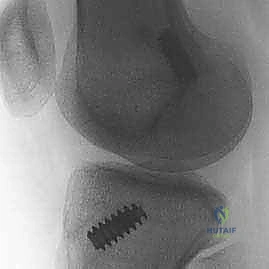

- الأشعة السينية (X-rays): تُطلب أولاً لنفي وجود أي كسور عظمية مصاحبة، مثل كسر "سيجوند" (Segond Fracture) وهو كسر قلعي صغير في الجانب الخارجي للقصبة يُعتبر علامة شبه مؤكدة لتمزق الرباط الصليبي.

خطوات العملية الجراحية بالتفصيل مع الأستاذ الدكتور محمد هطيف

تُجرى العملية تحت التخدير النصفي أو الكلي، وتستغرق عادةً من ساعة إلى ساعة ونصف. الدقة في هذه الخطوات هي ما يميز الخبير عن غيره.